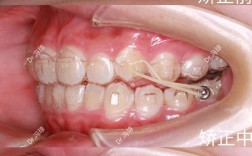

- 替牙期(6-10岁):这是“颌骨生长发育的快速期”,也是纠正功能性错颌的关键阶段,常见问题包括上颌前突(“龅牙”)、下颌后缩、个别牙反颌、牙列间隙异常等,此时可通过功能矫治器(如FRⅢ矫治器、Twin Block)刺激或抑制颌骨生长,改善上下颌骨关系,为恒牙排列创造空间。

- 功能矫治器:主要用于替牙期,通过调整颌骨肌肉功能引导颌骨生长,如“Twin Block”纠正下颌后缩,“FRⅢ”矫治器改善上颌前突,优点是可干预颌骨发育异常,降低成年后正颌手术概率;缺点是适用范围有限,需在特定年龄段使用。